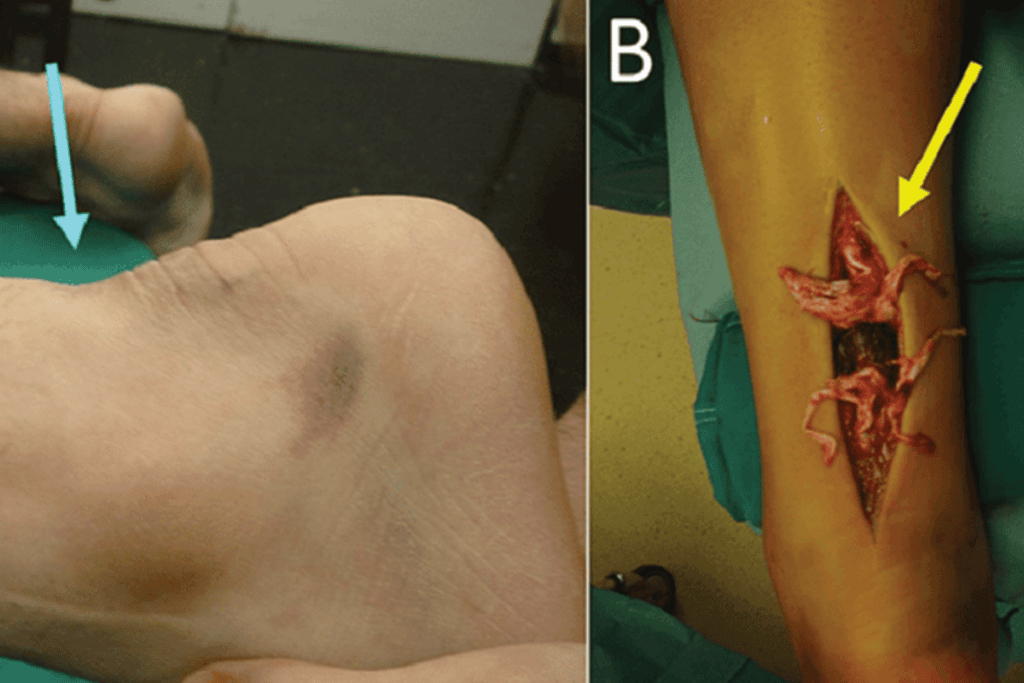

- widoczna deformacja w okolicy ścięgna – zapadnięcie w miejscu przerwania, które można wyczuć palcem.

- z czasem pojawia się obrzęk i zasinienie – widoczne w okolicy stawu skokowego i dolnej części łydki.

Leczenie operacyjne jest wskazane u pacjentów młodszych, aktywnych sportowo oraz w przypadkach zerwań ze znacznym rozejściem kikutów (> 1 cm). Stosuje się:

- techniki małoinwazyjne – pozwalają na zszycie ścięgna ze znacznie mniejszych, punktowych nacięć skóry; ryzyka związane z infekcją i gojeniem się ran pooperacyjnych są dużo mniejsze; minusem jest mniejsza kontrola nad układem włókien i ostateczną długością zszytego ścięgna,